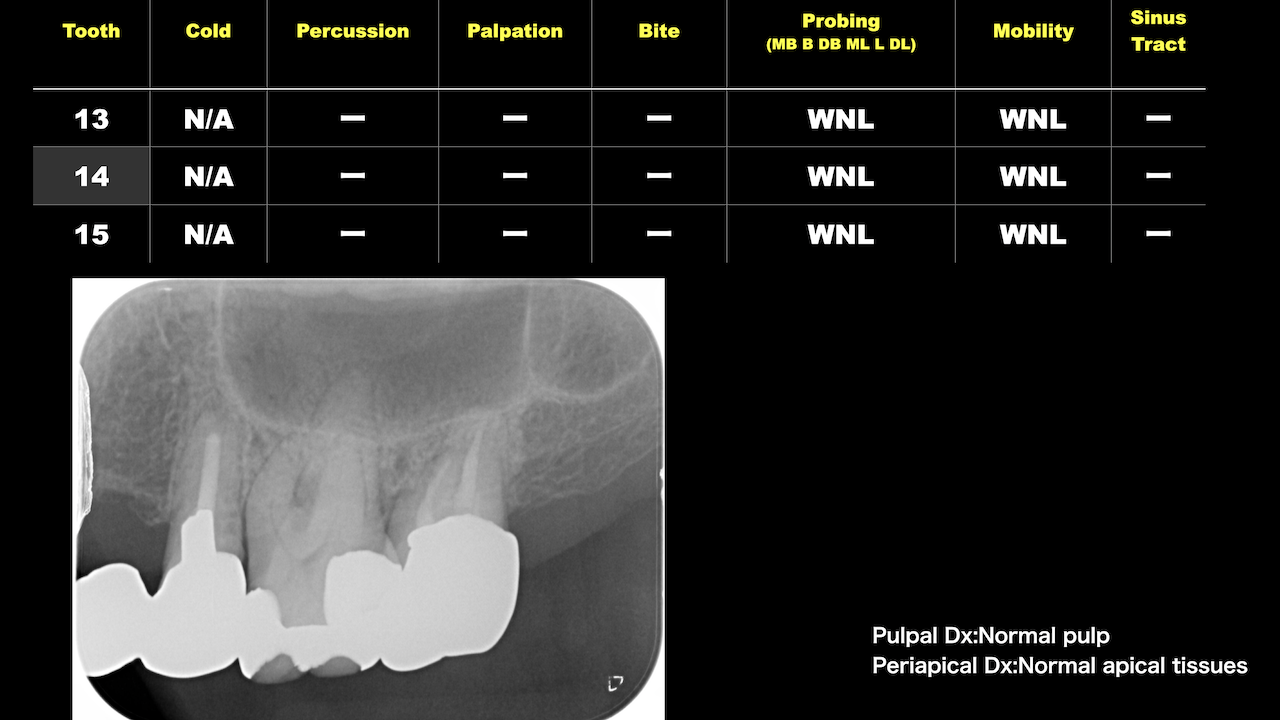

Implant近傍の#12,14に問題があるようだ。

それぞれ再根管治療した。

5ヶ月後にRecallすると、

#12,#14 MBの根尖病変は消失した。

これも非外科的歯内療法の威力が現れたケースだ。

だが、まだ4ヶ月である。

この後も問題が起きるかもしれない。

その時に解決策になるのは外科治療しかないのである。